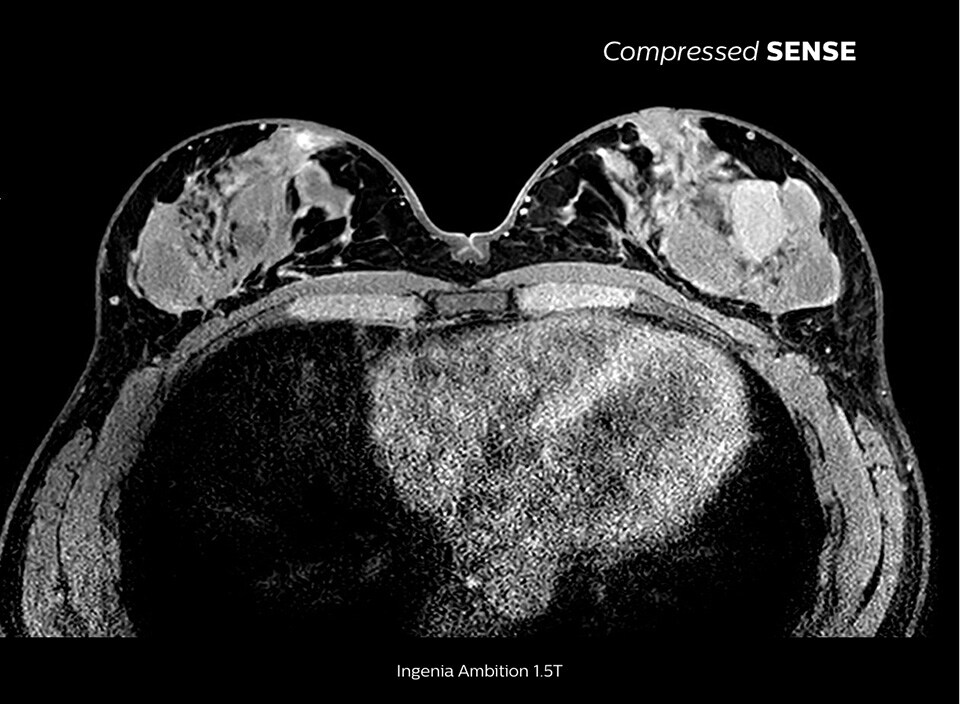

Compressed SENSE

Up to 50% faster MRI scans with virtually equal image quality1

Philips Compressed SENSE is a cutting-edge MRI technology that significantly speeds up scans while delivering virtually equal image quality. By intelligently compressing data, it accelerates your existing MR scans by up to 50%, frees up time to improve your patient experience and can provide up to 60% higher resolution to enhance diagnostic confidence.1 Philips Compressed SENSE is suitable for all anatomies and can be used for all anatomical contrasts, in both 2D and 3D.